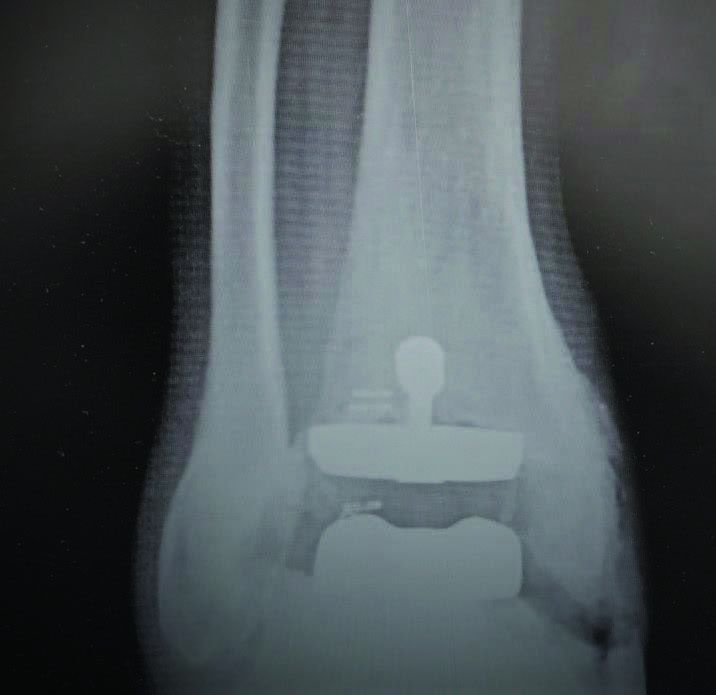

- Joint fusion using plates, screws, or rods

X-ray or CT/MRI

What imaging tests are needed before the surgery?

X-rays, CT scans, or MRI are used to understand the damage and plan the surgery with precision.

What materials are used for fixation?

Plates, screws, rods, or bone grafts may be used to support the bones while they fuse.